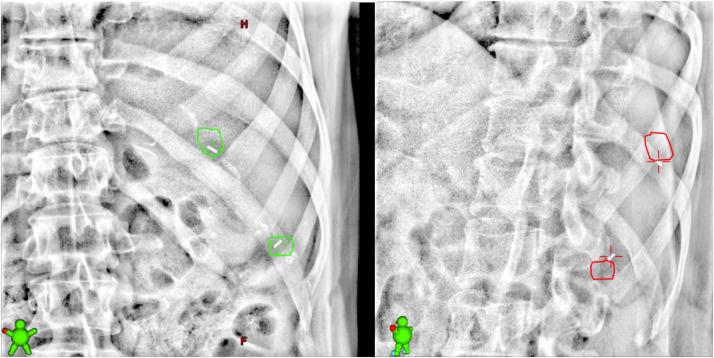

Data from 33 patients treated with 41 courses of liver SBRT were analyzed. During treatment, planar kV images orthogonal to the treatment beam were acquired to determine treatment interventions, namely treatment pauses (ie, adequacy of gating thresholds) or treatment shifts. Patients were shifted if internal markers were >3 mm, corresponding to the PTV margin used, from the expected reference condition. The frequency, duration, and nature of treatment interventions (ie, pause vs shift) were recorded, and the dosimetric impact associated with treatment shifts was estimated using a machine learning dosimetric model.

Of all fractions delivered, 39% required intervention, which took on average 1.9 ± 1.6 minutes and occurred more frequently in treatments lasting longer than 7 minutes. The median realignment shift was 5.7 mm in size, and the effect of these shifts on minimum tumor dose in simulated clinical scenarios ranged from 0% to 50% of prescription dose per fraction.